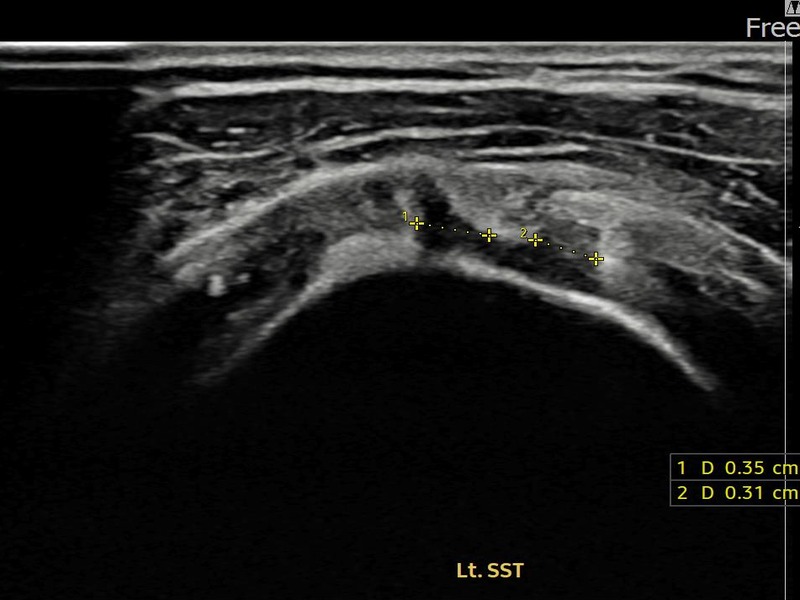

정ㅇㅇ님 · 좌측 극상근건 부분파열

좌측 어깨 통증이 오래 지속되어 내원하셨습니다. 초음파 검사에서 극상근건 부분파열이 확인되었으며, 어깨인대 축소봉합술 시행 후 장기 추적 초음파에서 힘줄 연속성이 완전히 회복된 것이 확인되었습니다.